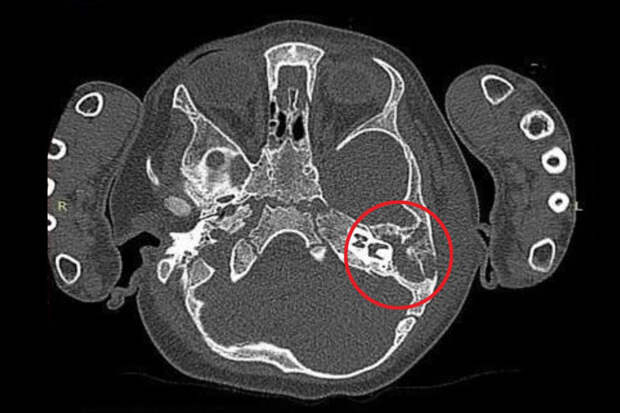

"Врачи Центра диагностировали тяжелое осложнение отита.

Гнойный воспалительный процесс уже перешел в мягкие ткани заушной области. Результаты компьютерной томографии подтвердили деструкцию костной стенки", - поделились в пресс-службе.Девочке провели экстренную операцию - сделали небольшой надрез, очистили полость от 3 мл гноя, а также от воспаленных тканей и установили дренаж. Медики заверили, что сейчас с пациенткой все хорошо, она уже дома.